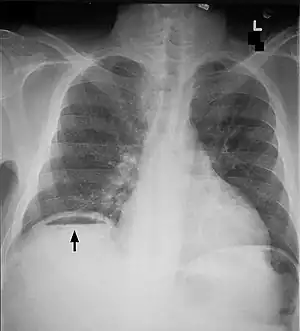

| Frontal chest X-ray. The air bubble below the right hemidiaphragm (on the left of the image) is a pneumoperitoneum. | |